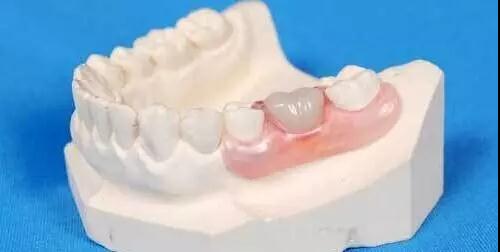

缺牙后多久修复

修复一般在拔牙2~3个月后进行

拔牙前须考虑好以后镶假牙的设计问题

(图为镶假牙)

拔牙1个月后可以镶活动义齿

(图为活动义齿)

2~3个月后可镶固定义齿

(图为固定假牙)

半年后才能种植牙

(图为种植牙)

迫切希望拔牙后就能镶假牙的患者

可以采用“即刻义齿”技术

而对于希望镶“种植义齿”的患者

则需要等待更长的时间(半年至一年)